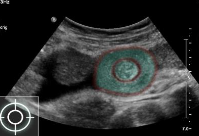

Target sign in intussusception

Ultrasound abdomen (bowel; transverse plane)

Concentric alternating hyperechoic and hypoechoic rings are visible.. Together the alternating

layers produce a target-like appearance (target sign)